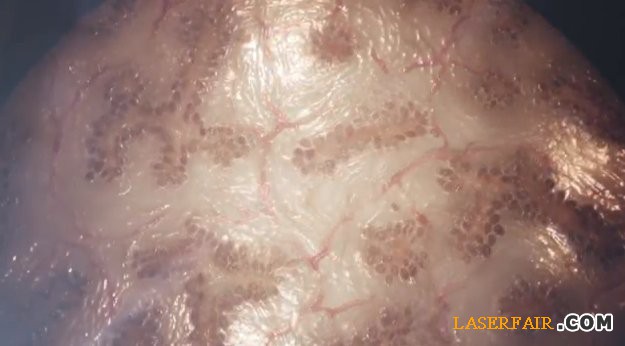

Organovo 3D打印的肝髒組織樣品